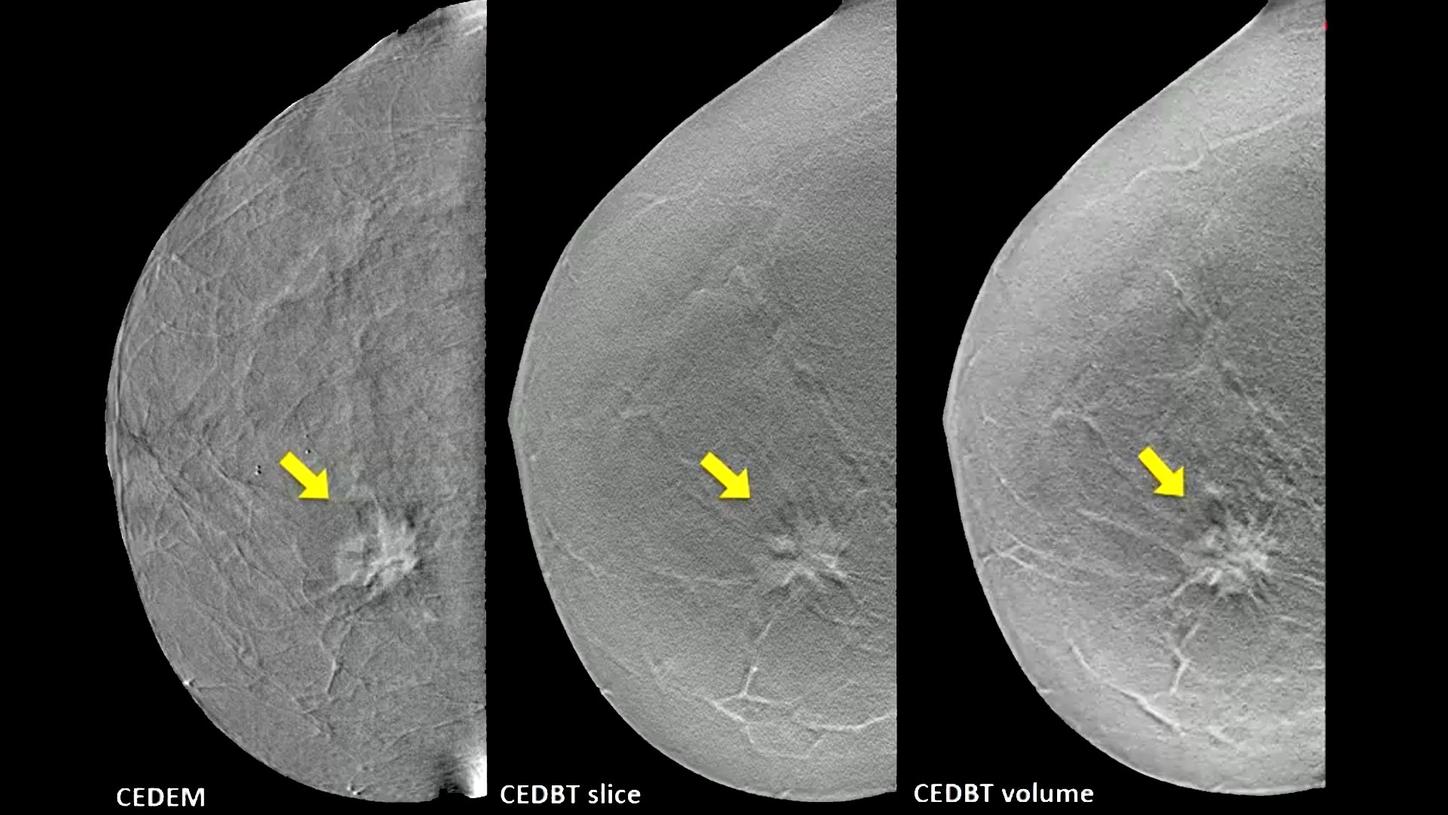

Profit from expert knowledge across all imaging modalities with a global player: Siemens Healthineers